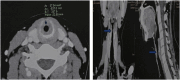

Introduction and importance: Idiopathic subglottic stenosis is a rare condition that primarily affects young women, with an etiology that remains poorly understood.

Case presentation: We report two cases of patients presenting with acute laryngeal dyspnea secondary to idiopathic subglottic stenosis. Clinical and paraclinical evaluations ruled out infectious, immunological, and iatrogenic causes. Treatment consisted of endoscopic procedures, including balloon dilation, CO₂ laser vaporization, and intralesional injections of corticosteroids and 5-fluorouracil. One patient required CO₂ laser incision of the inferior constrictor muscle due to recurrence. After prolonged follow-up, the clinical outcome was favorable, with no significant recurrence.

Clinical discussion: The etiology of idiopathic subglottic stenosis remains uncertain. A plethora of therapeutic alternatives have been proposed; however, none has demonstrated superiority in terms of ease and efficacy. Until more is known about the condition, prolonged postoperative clinical, radiological, and endoscopic monitoring is essential, even in cases where only the slightest recurrence of clinical signs is observed.